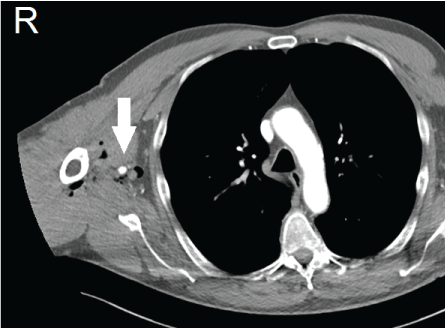

A seventy one-year-old man was presented to the emergency department in October 2016. He was working on the farm of his son when he got trapped between hydraulic closing doors of a truck. He sustained trauma to his head and to his right arm. His medical history consisted of a transient ischemic attack and chronic obstructive pulmonary disease (GOLD classification 2). He was using pulmonary medication and a combination of carbaspirin calcium (100 mg once a day) and dipyridamole (200 mg twice a day). Trauma care was conform advanced trauma life support principles. Initial presentation showed a hemodynamically stable patient with full consciousness with a laceration of his head and bruising to the right arm. The X-ray imaging of thorax and pelvis, the focussed assessment with sonography for trauma, blood analyses and electrocardiogram were normal. A secondary survey showed a laceration on the medial aspect of the right upper arm with bruising and swelling. The capillary refill of his right arm was delayed and peripheral pulses were absent. A pulse oximetry measurement on the right index finger showed 95% saturation. The arterial pressure on the right could not be measured and on the left measured 144/72 millimetres of mercury. His right arm had diminished motoric functioning and sensibility was severely impaired. A regular X-ray of his right arm showed no fractures but did show air configurations in the subcutaneous tissue (Figure 1). An additional computed tomography of cerebrum and cervical vertebrae showed no abnormalities. In the same session a CT-angiography of the right arm was performed. The Ct showed subcutaneous air surrounding the brachial artery with a dissection and segmental thrombosis (Figure 2 and Figure 3). The neurologist made a careful neurological examination while the trauma surgeon cleared the patient for the operation. Directly after the trauma resuscitation he was brought to the hybrid operation room to perform surgery. General anaesthesia was given to the patient to facilitate a direct conversion to open surgery if necessary. A sterile exposure was made for both groins and the right arm and cervical area. A duplex ultrasound guided retrograde puncture of the right common femoral artery and placement of a 6 French sheath gave access. After gaining arterial access systemic heparin was administered (5000 international units). With a Terumo guidewire (0.035") [Terumo Europe NV, Belgium] and a SIM1 catheter [Cordis Corporation, USA] the axillary artery was reached through the brachiocephalic trunk. A digital subtraction angiography showed a traumatic dissection of the proximal brachial artery (Figure 4). In a gentle twisting fashion the 0.035 guide wire was advanced through the lesion follow by the catheter. An angiography through the catheter, distal to the lesion, confirmed intraluminal positioning of the catheter. After this recanalization the SIM1 catheter was exchanges for a Multi-purpose catheter [Cordis Corporation, USA]. A smaller guidewire (0.018") was placed and a 6 mm balloon angioplasty was performed. After angioplasty two 5 mm × 100 mm Supera [Abbot, USA] stent grafts were deployed in telescopic fashion with the distal stent being deployed first (Figure 5). The control angiography showed a good positioning of the stent grafts (Figure 6). The puncture site was closed with a Star close closure device [Abbot, USA]. After surgery distal pulsations at the wrist had restored and the sensory impairment was recovering. During the first 2 post-operative days the motoric disability markedly improved to nearly normal. Postoperative recovery was without complications. Patient received dual platelet anticoagulation (carbasparin calcium 100 mg once a day and clopidogrel 75 mg once a day) for the first 3 months. After three months his own pre-trauma anticoagulation therapy was restarted (carbaspirin calcium and dipyridamole). A control CT-angiography at 4 months post-operatively showed patent stent grafts with good deployment. Duplex-ultrasound imaging of the stent grafts showed patent stents at 6 months follow up. Unfortunately the patient did sustain concomitant neurological damage to the brachial nerves plexus at trauma. At 4 months post-operatively the neurosurgeon planned a decompression of the ulnar nerve. To date nearly all motoric functioning of his arm recovered except for fine motoric functioning.

Figure 2: Subcutaneous air on CT surrounding right arteria brachialis. View Figure 2